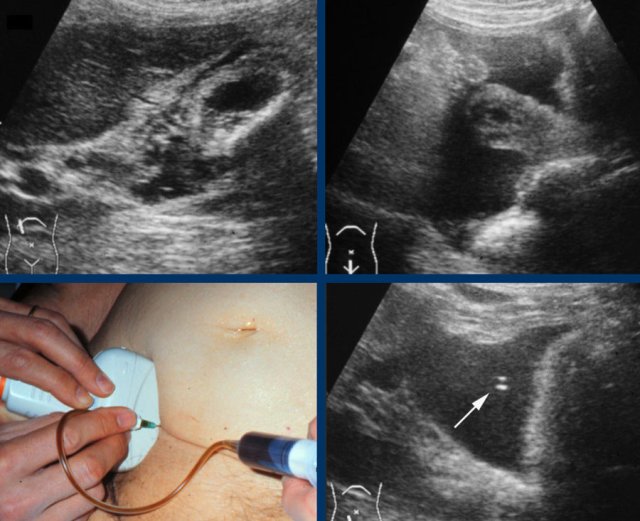

The hydrops sign is tested by applying graded compression over the gallbladder.

The hydrops-sign is positive if the gallbladder during compression “bulges” into the abdominal wall and keeps its rounded contour (fig).

This is best seen in expiration, when the abdominal wall muscles relax.

Here we can see how the hydropic gallbladder will keeps its rounded shape during compression.

Here images of a patient with acute hydrops of the gallbladder, visualized in its longitudinal and its axial plane.

The obstructing stone is impacted (arrow).

Note that during compression the hydropic gallbladder bulges into the abdominal wall (arrowheads), indicating high intraluminal pressure.

It is however not always possible to visualize the hydrops-sign reliably, especially when the gallbladder lies high under the right costal arch.